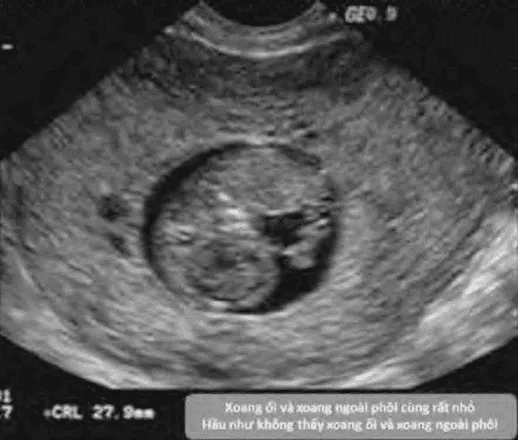

- Trứng trống (blighted ovum): Chỉ sự hiện diện của túi thai nhưng không thấy phôi thai bên trong.

Để chẩn đoán trứng trống, không đủ khi chỉ không thấy phôi hoặc túi noãn hoàng với MSD < 25 mm. Phải có MSD ≥ 25 mm không thấy phôi hoặc túi noãn hoàng.

- CRL ≥ 7 mm không thấy tim thai.

- MSD ≥ 25 mm không thấy phôi thai.